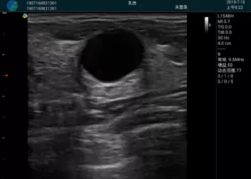

M20查看:囊內回聲均勻,邊界清晰,囊壁光滑

M20引導抽吸術(shù)后囊腫消失,原區域空腔形成,脂肪層與腺體層架構發(fā)生改變